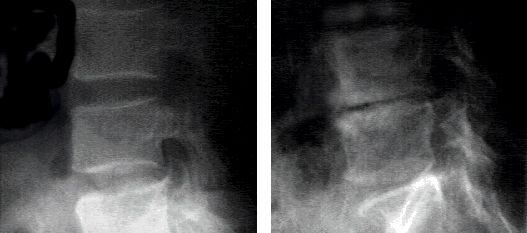

We don’t take x-rays (radiographs) on every first visit

Unlike some chiropractors, we think it’s unethical, unnecessary, and hazardous to take radiographs (“x-rays”) on every single patient on the first visit.  Some doctors use x-rays in place of a good history and exam, and some use them to scare patients into getting more treatment. Unless there are “red flags” (things that suggest serious underlying pathology), or acute trauma/injury (a fall, auto accident, direct blow to an area, etc), there isn’t much need for taking xrays and exposing patients to unnecessary radiation. As a chiropractor, if you do a good exam and take a good history, you should have a pretty good idea what is going on with the patient, making x-rays unnecessary.